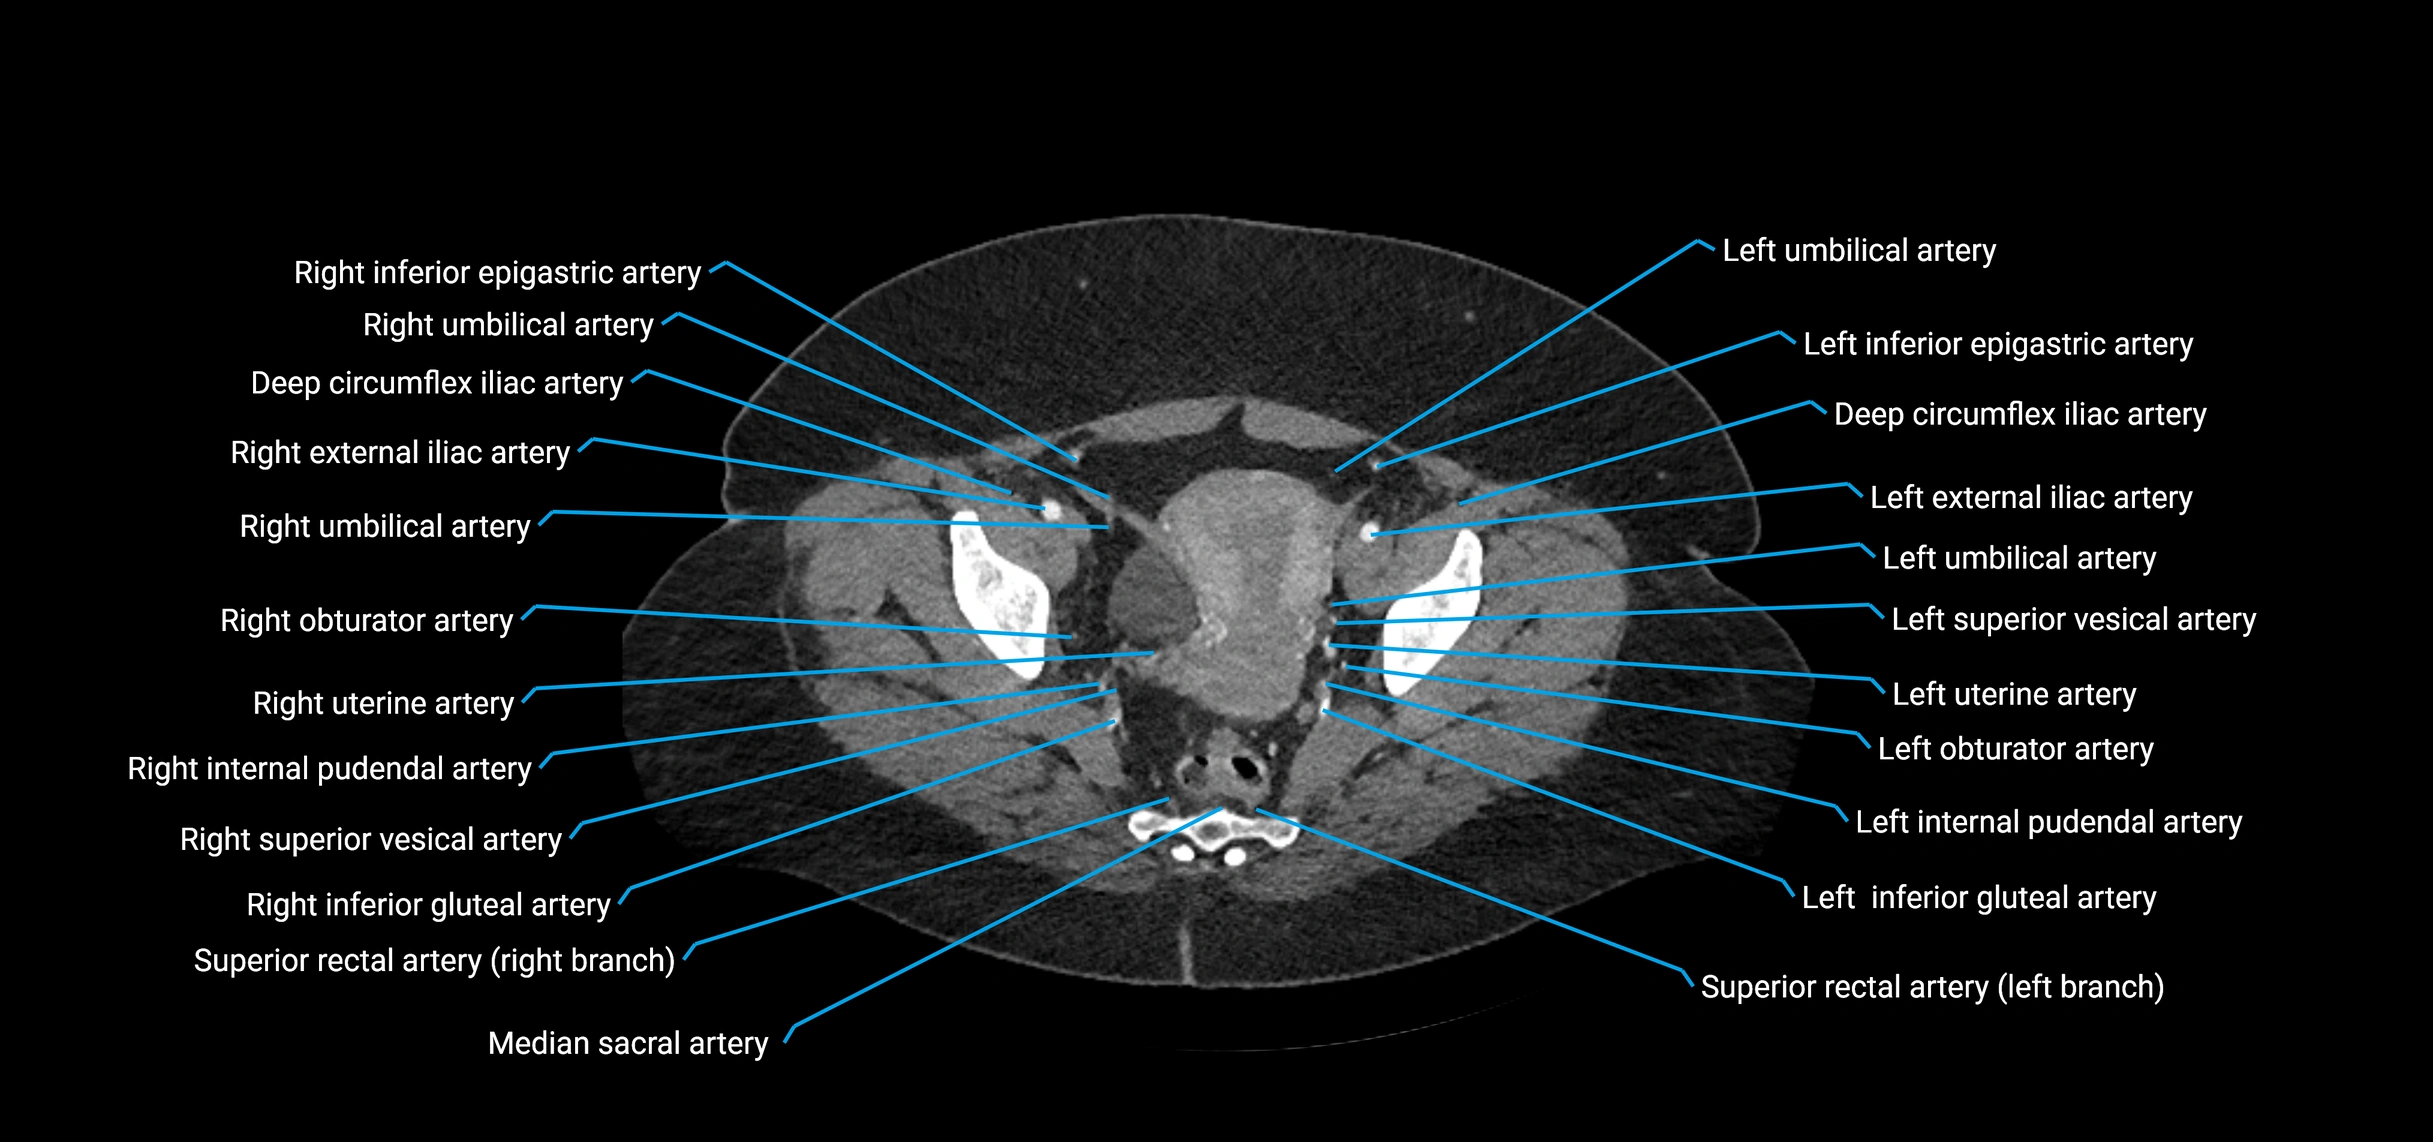

Contrast-enhanced CT (CTA):

• Gold standard for abdominal aortic imaging

• Provides excellent detail of lumen, wall, aneurysm, thrombus, and branch vessels

• Multiplanar and 3D reconstructions help in aneurysm measurement, stent graft planning, and dissection evaluation

• Detects acute rupture, traumatic injury, or occlusion with high sensitivity